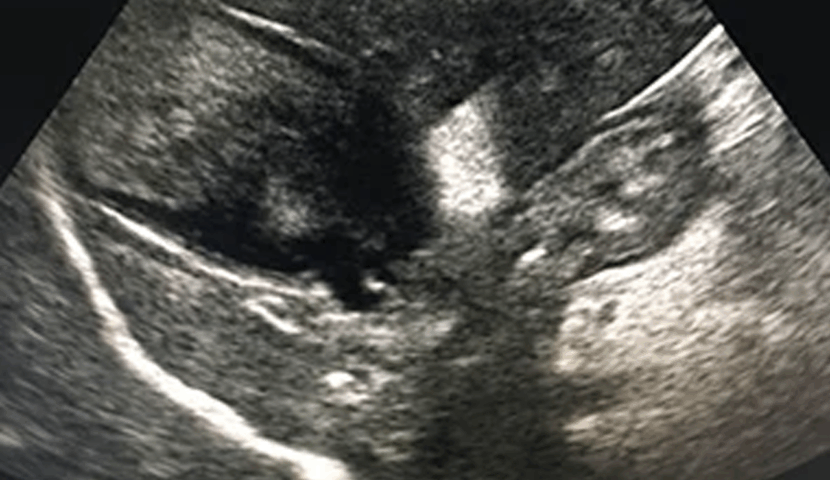

身体検査で黄疸を確認。血液検査で重度の肝数値の上昇、超音波検査で胆嚢内に粘液が重度に貯留し、拡張した胆嚢と胆嚢周囲の炎症を疑う所見を確認。

| 本症例は胆嚢粘液嚢腫および急性胆嚢炎と診断。手術自体は迅速に終了しましたが、急性胆嚢炎に伴う腹腔内臓器の障害もあり、長期入院が必要となりました。 退院後も定期的な通院にて肝臓や腎臓のケアを行っています。やはり状態が悪くなってからの手術は、術後の管理が難しく合併症も多いことから、その後もさまざまなケアが必要になってきます。 状態が悪くなる前の早期の診断・治療が重要です。 |